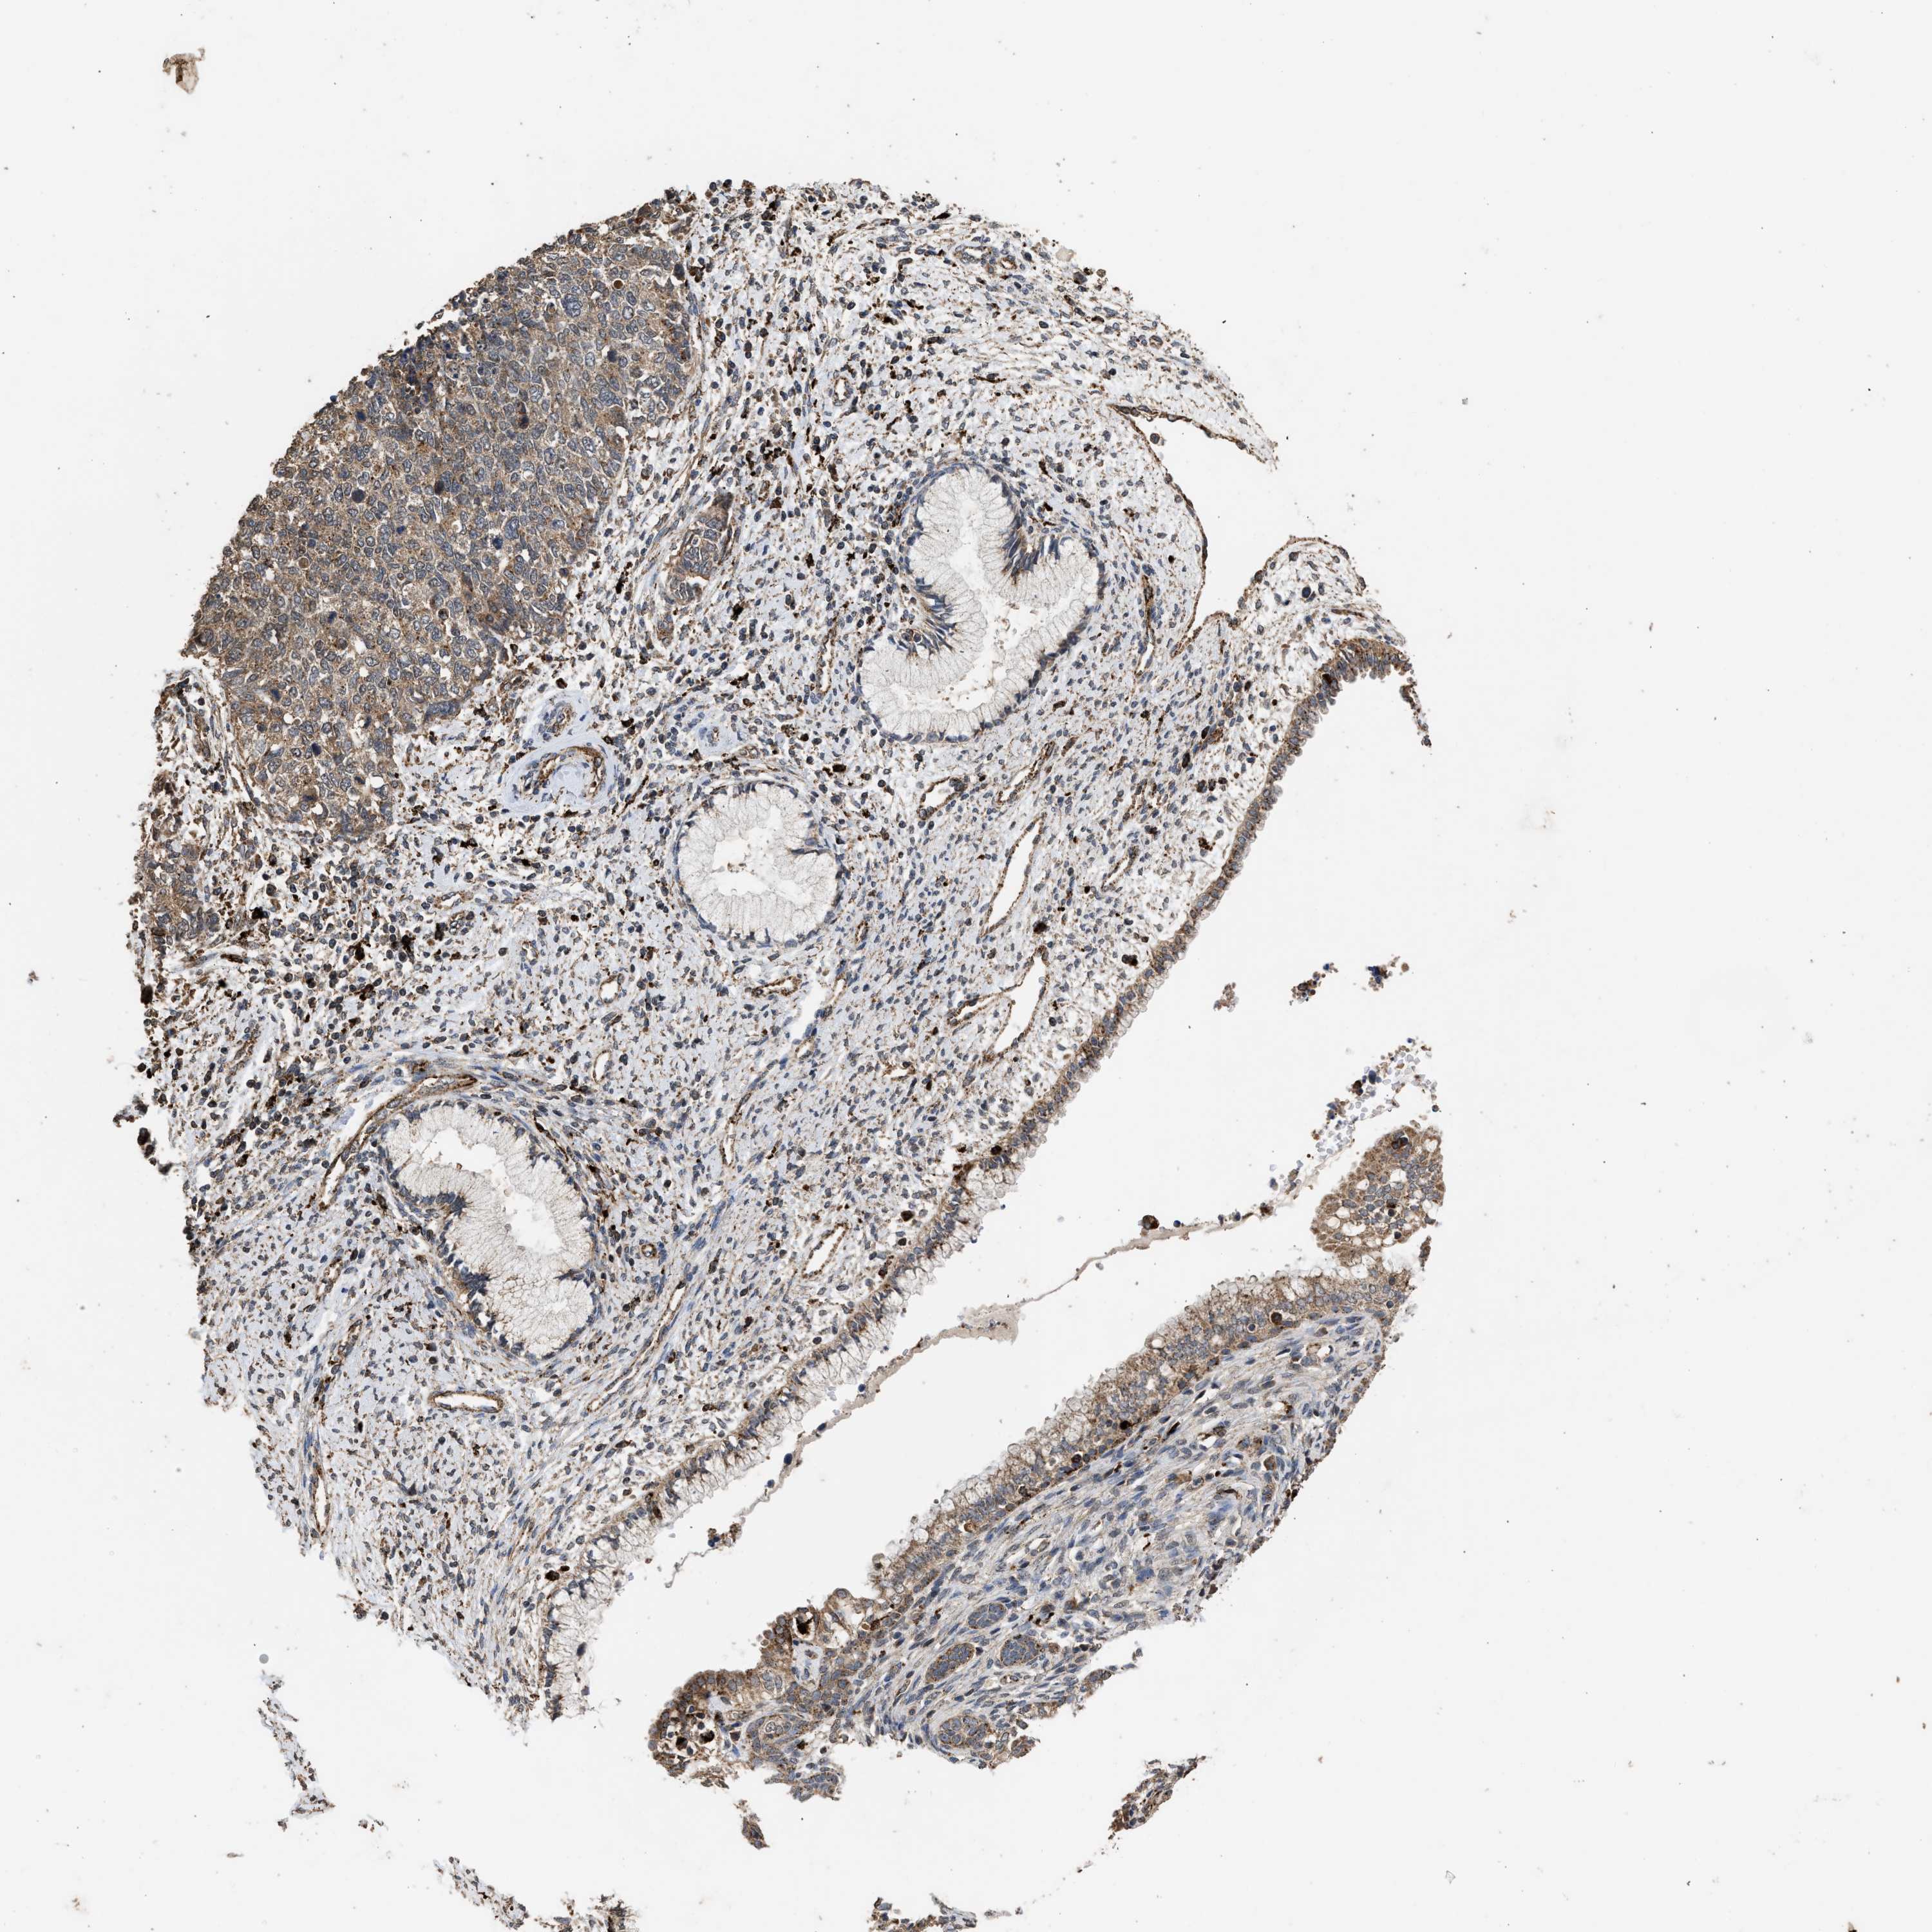

CERVICAL CANCER - Protein expressioni

A mouse-over function shows sample information and annotation data. Click on an image to view it in a full screen mode. Samples can be filtered based on level of antibody staining by selecting one or several of the following categories: high, medium, low and not detected. The assay and annotation is described here.

Note that samples used for immunohistochemistry by the Human Protein Atlas do not correspond to samples in the TCGA dataset.

Antibody stainingi

Antibody staining in the annotated cell types in the current human tissue is reported as not detected, low, medium, or high, based on conventional immunohistochemistry profiling in selected tissues. This score is based on the combination of the staining intensity and fraction of stained cells.

Each image is clickable and will lead to virtual microscopy that enables deeper exploration of all samples and also displays staining intensity scores, fraction scores and subcellular localization as well as patient and tissue information for each sample.

Antibody CAB017112

Staining

High

Medium

Low

Not detected

Intensity

Strong

Moderate

Weak

Negative

Quantity

>75%

75%-25%

<25%

None

Location

Nuclear

Cytoplasmic/membranous

Cytoplasmic/membranous,nuclear

Squamous cell carcinoma, NOS

Adenocarcinoma, NOS